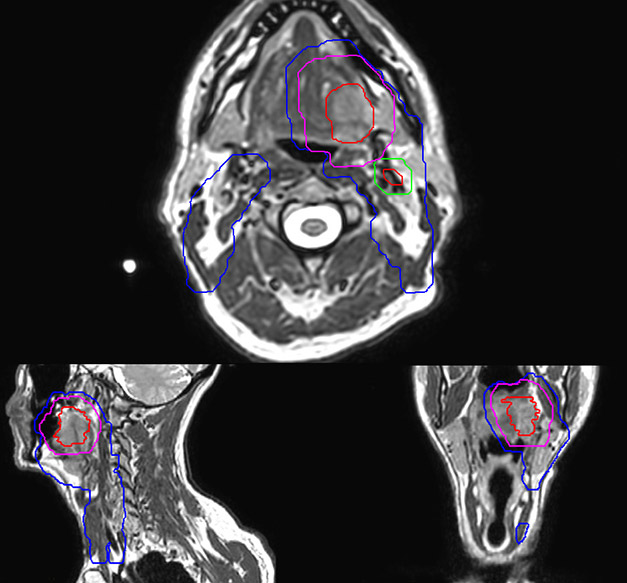

Epidermoid carcinoma of the left tongue base

The patient was diagnosed with an epidermoid carcinoma of the base of the left invading the amygdala lodge and the amygdaloglossal groove. Radiochemotherapy with curative aim was prescribed with a dose of 70 Gy for the tumor, 66 Gy on the suspicious nodes and 56 Gy on the elective drainage areas - in 33 fractions.

Simulation imaging

MR-based contouring and planning

MR based target contouring

MR-based target contouring on 3D T2W TSE in transversal, sagittal

and coronal planes.

Personalized VMAT dose

Personalized VMAT dose planned in Philips Pinnacle.